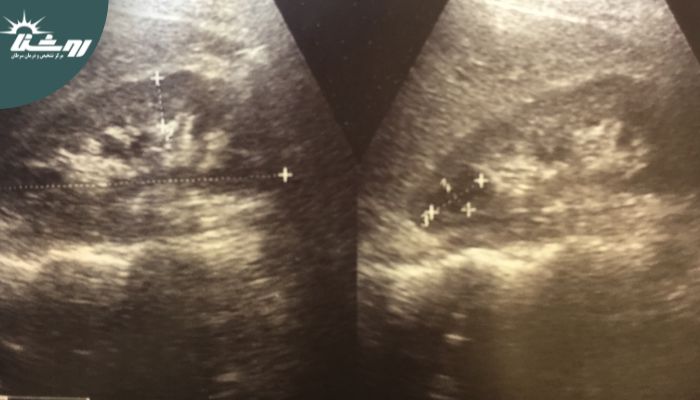

برای تشخیص کیستهای کلیه، پزشکان معمولاً از روشهای تصویربرداری نظیر سونوگرافی، سیتی اسکن، یا MRI استفاده میکنند. این روشها به تعیین محل دقیق، اندازه، و ساختار کیستها کمک میکنند و در تصمیمگیری برای نیاز به درمان یا نظارت بیشتر مؤثر هستند. مرکز تصویربرداری روشنا بهترین مرکز سونوگرافی در غرب تهران شناخته شده است که خدمات تصویربرداری دقیق با استفاده از دستگاههای پیشرفته و تیمی از متخصصان با تجربه ارائه میدهد. استفاده از این مرکز برای اطمینان از دقت تشخیص و کیفیت بالای خدمات توصیه میشود.